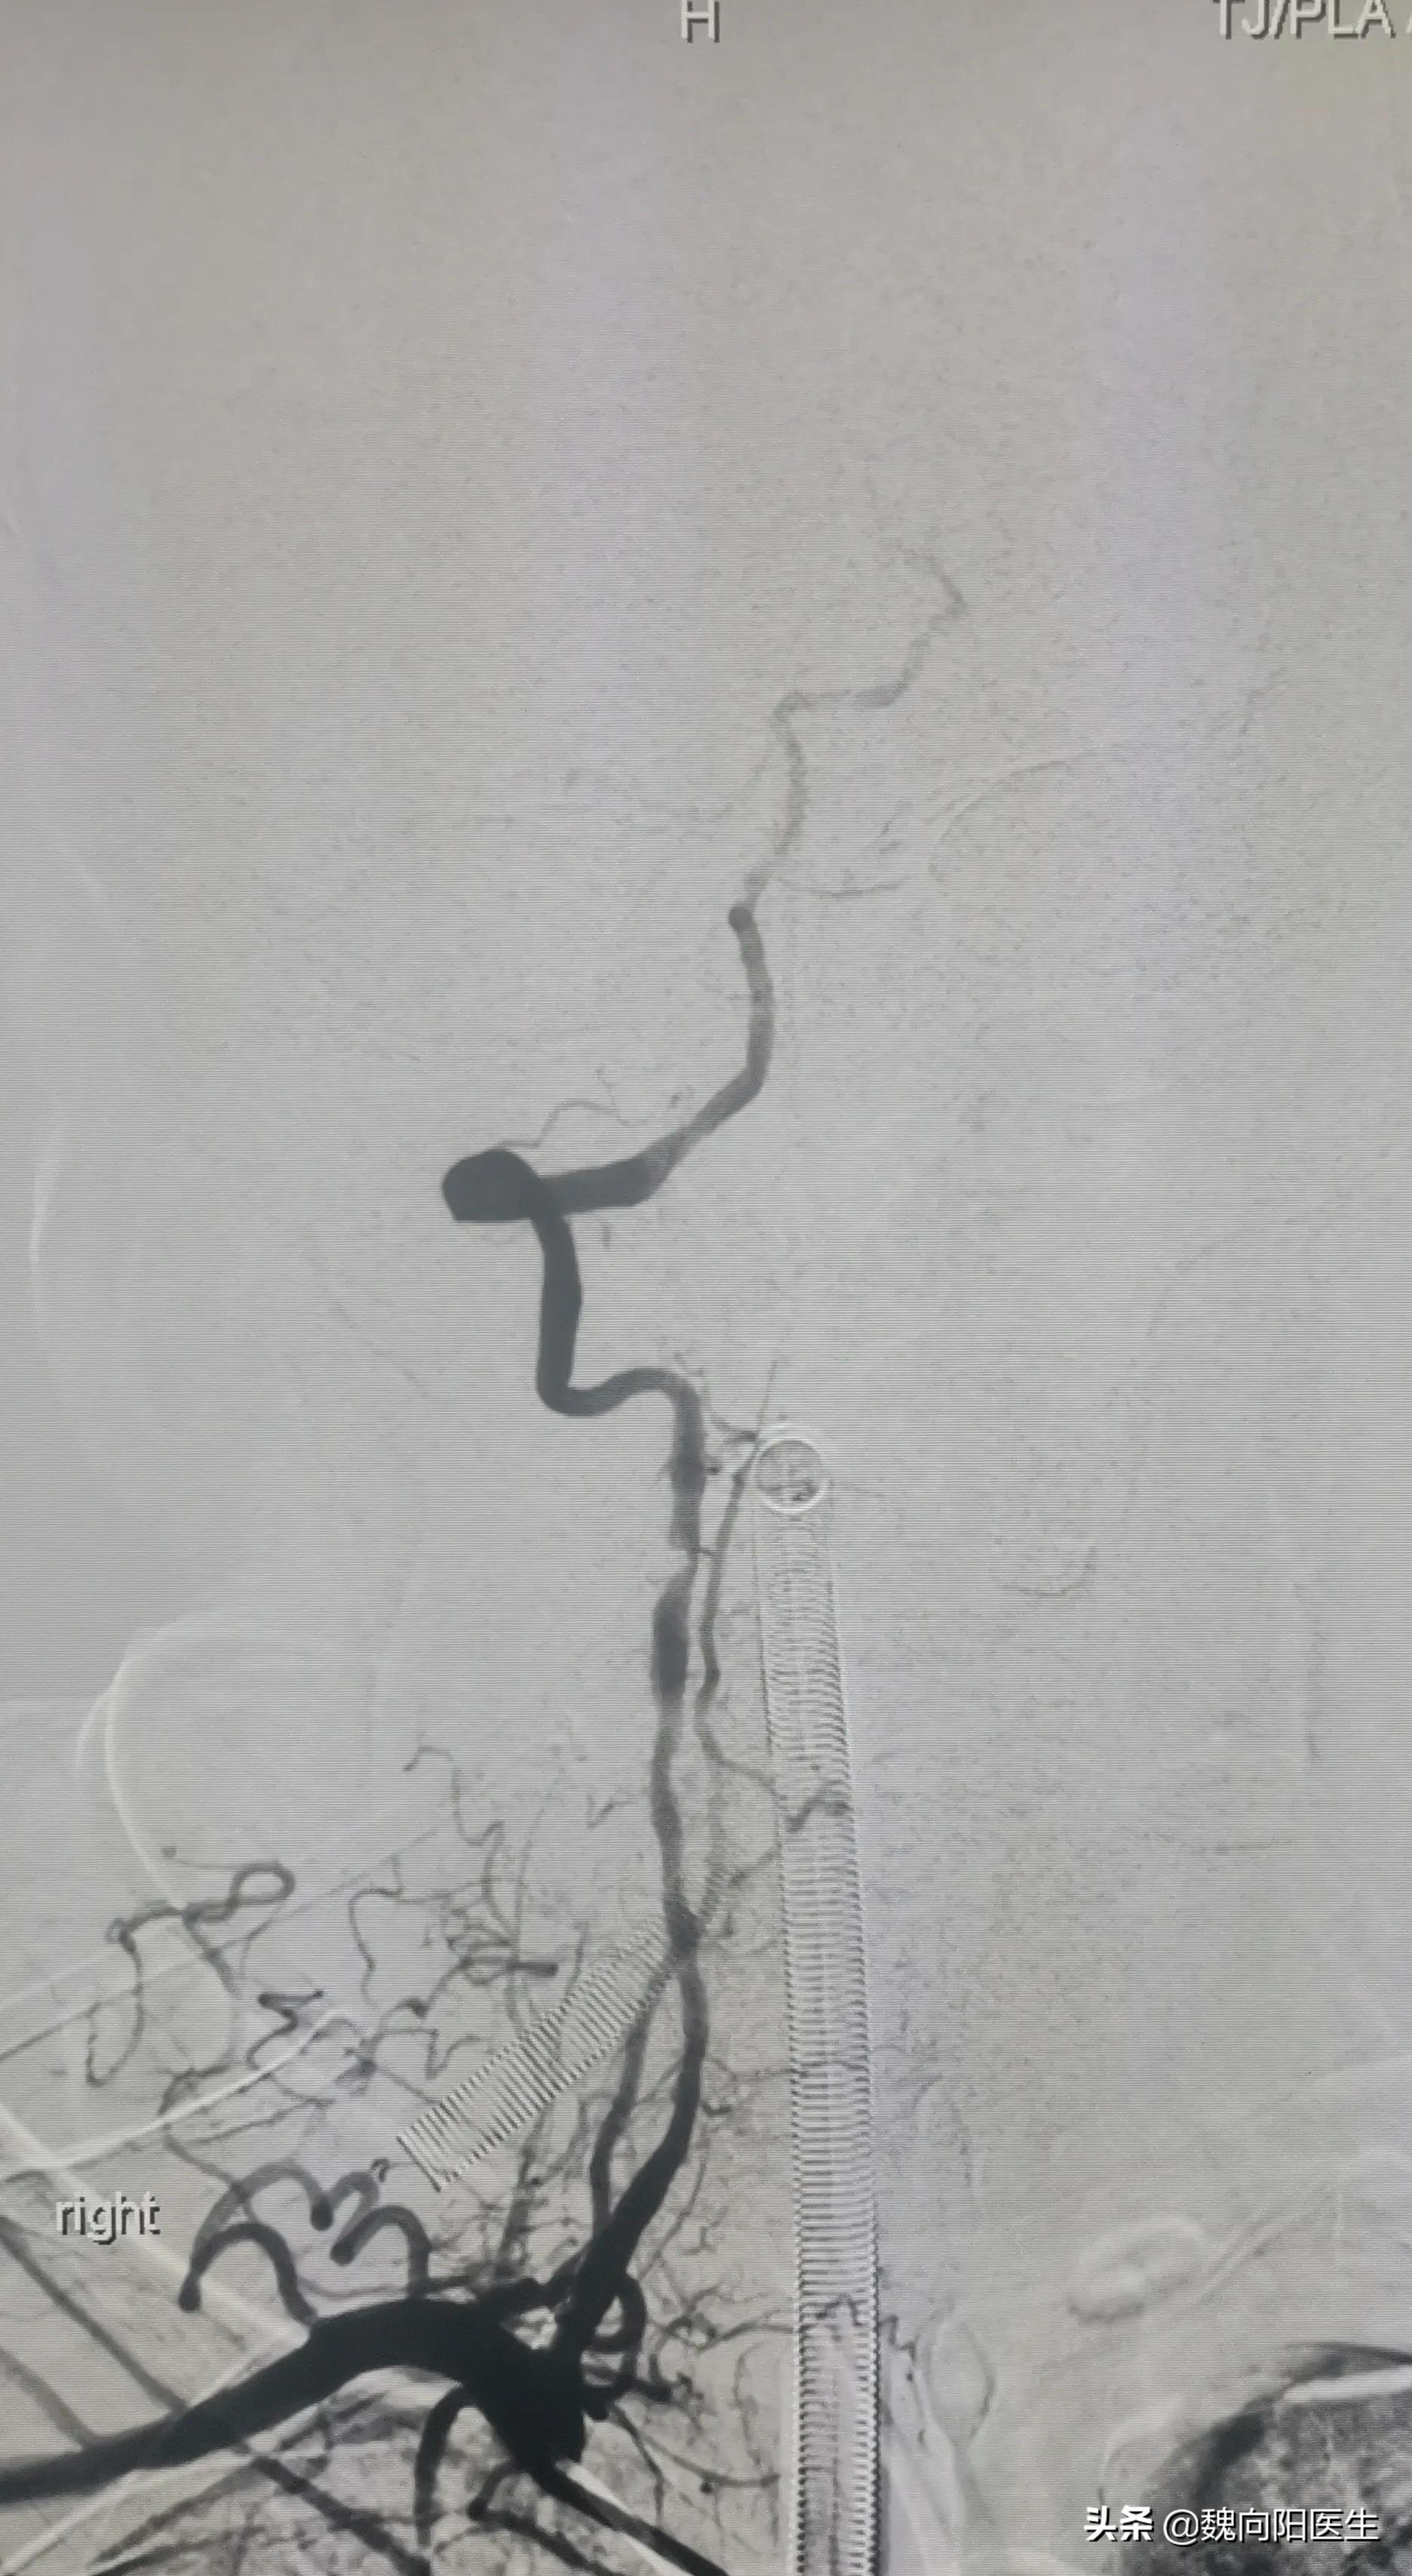

立即给球囊扩张+支架植入,患者狭窄消失,远端血流通畅,大脑重新恢复供血。

术后复查CT提示:脑干造影剂渗漏,考虑脑干梗死导致。(脑干梗死体积较大)